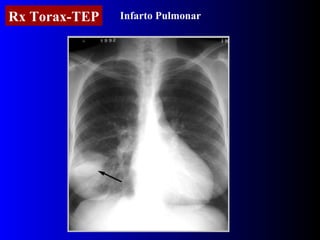

Rx Torax-TEP Infarto Pulmonar

Radiografía de torax Puede ser normal  en un 12-15% En el grupo restante los signos son inespecíficos Aumento de arteria pulmonar descendente derecha 67 % ( s. Pallas ) Elevacion diafragmática 62 % Cardiomegalia 56 % Derrame pleural 52 % Joroba de hampton 25% Oligohemia 12 a 20% ( s. Wastermark )